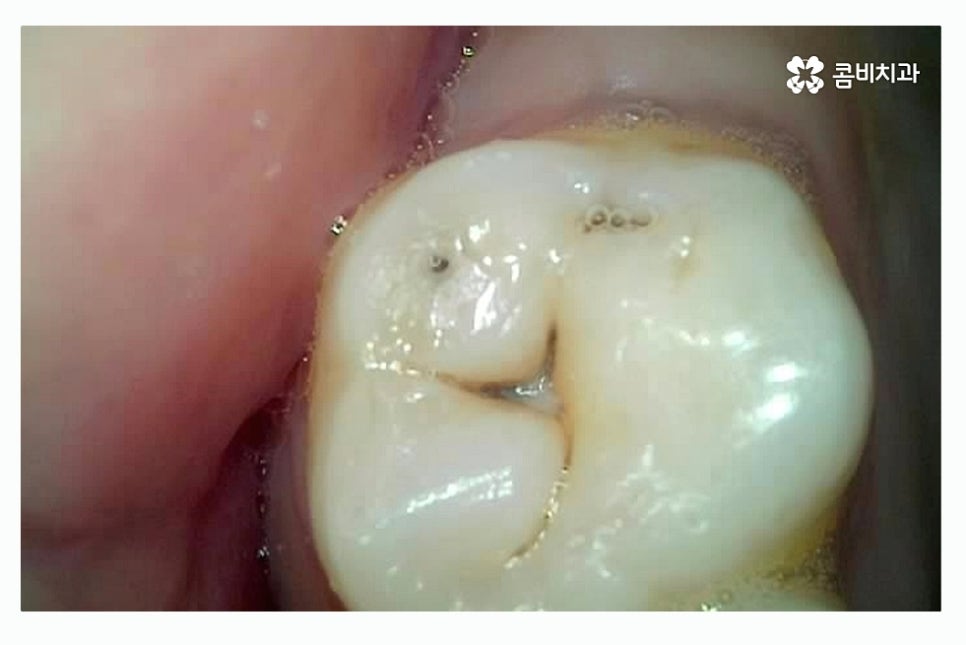

충치의 대표적인 증상은 시림, 통증, 구취가 대표적이지만

충치 초기에는 별다른 증상이 없이 까만 점으로 나타나는 경우가 많으며

치아 사이 혹은 내부의 경우에는 눈으로 확인도 어려울뿐더러

증상으로 충치를 느끼는 시점에서는 이미 충치가 상당히 진행된 경우가

많기 때문에 주기적인 검진을 통해서 초기 발견과 치료를 하는 것이 중요하다고 볼 수 있어요.